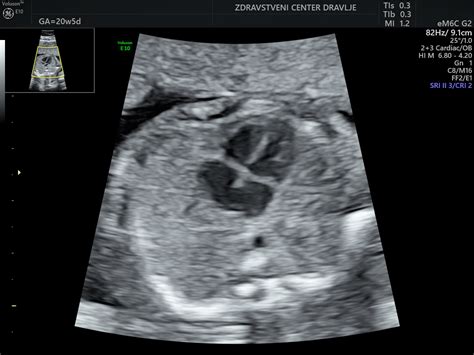

V 11. tednu nosečnosti vaš otrok dosega pomembno fazo hitre rasti. Čeprav v dolžino meri še vedno le okoli 4-5 cm, kar je primerljivo z velikostjo limone, so njegovi notranji organi, kot so možgani, pljuča, jetra in ledvice, že skoraj v celoti razviti. Srce, ki se je začelo razvijati že prej, je sedaj strukturno dokončano in zanesljivo utripa s frekvenco med 140 in 170 udarci na minuto. Ginekolog lahko s pomočjo ročnega Dopplerja že zazna ta srčni utrip. V tem tednu se zaključi tudi proces, ki je omogočil popolno ločitev prstov na rokah in nogah, saj je programirana celična smrt (apoptoza) razgradila tkivo med njimi. Zasnove nohtov se prav tako oblikujejo.